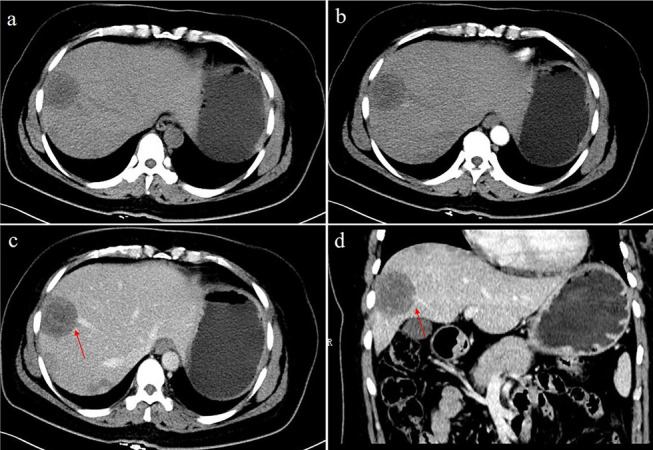

The solitary nodular type was detected in 3 patients (3/20, 15%), including 3 solitary lesions, all of which were located in the right lobe of the liver. Only 1 patient showed heterogeneous density with spot calcification; the other patients showed homogeneous density. One patient exhibited peripheral nodular enhancement, with enlarged feeding arteries and hyper-perfusion in the arterial phase. A “target” sign and portal vein branch invasion were detected in one patient (Fig. 2).

Fig. 2.

A 41-year-old female with solitary nodular type HEH. An axial unenhanced CT image a shows a round nodule with ill-defined, heterogeneous hypodensity. An axial arterial phase image (b) shows rink-like enhancement. An axial portal phase image (c) shows “target” sign enhancement. Coronal reconstruction of the portal venous phase (d) shows a narrowing portal vein branch adjacent to the lesion. This patient was initially misdiagnosed with hepatic abscesses. On follow-up CT performed 10 months after resection (e, f), a new lesion was detected in the right lobe of the liver (red arrowheads)